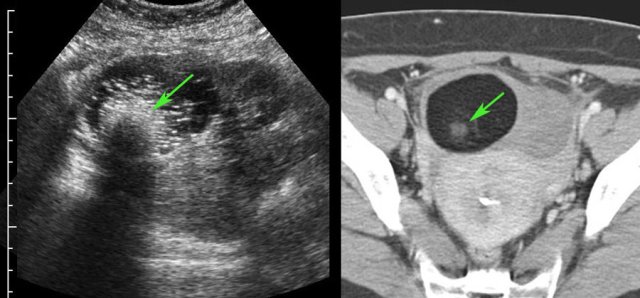

In this young woman a conspicuous hemorrhagic right

ovarian cyst (arrowheads) was visualized and initially held responsible

for her RLQ symptoms.

Further examination however revealed an acute appendicitis

(arrow).

The cyst was an asymptomatic coincidental finding.